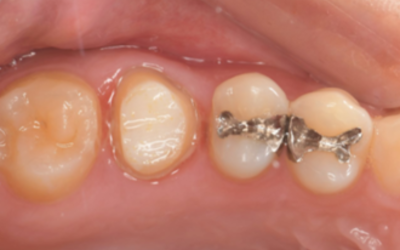

移植3ヶ月後の口腔内写真

移植3ヶ月後。

歯根周囲に透過像を認めるが動揺などはなく、歯周ポケットも形成されていなかった。